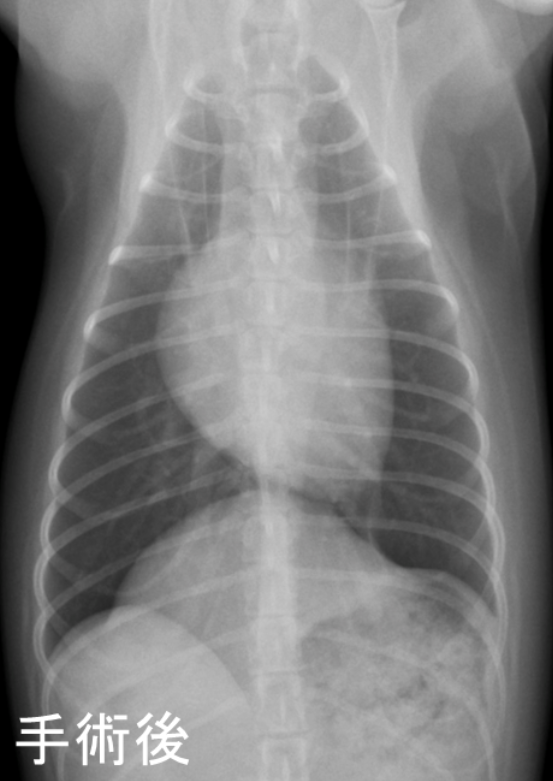

ショック状態が改善した後、胃や脾臓を腹腔内へ戻してヘルニア孔を閉じる手術を行い、現在手術から8ヵ月が経ちましたが再発もなく元気に過ごしています。

手術後のレントゲン画像